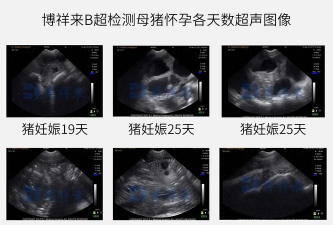

③实时超声波法:实时超声波在准确诊断初产母猪和经产母猪的早期妊娠方面颇具潜力。腹部实时超声波探查的传感器与其他诊断仪相同。超声波穿过子宫然后返回到传感器,若在生殖道内探测到明显的积液囊或胎儿则可确诊妊娠。